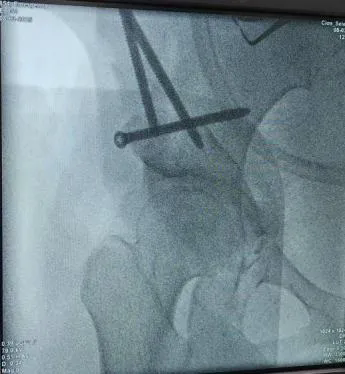

圖5-6:術中截骨